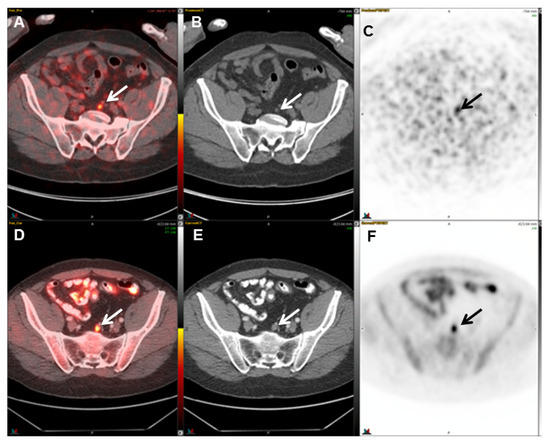

2.5.1. 68Ga-PSMA-11

- Rauscher, I.; Maurer, T.; Fendler, W.P.; Sommer, W.H.; Schwaiger, M.; Eiber, M. 68Ga-PSMA ligand PET/CT in patients with prostate cancer: How we review and report. Cancer Imaging 2016, 16, 14. [Google Scholar] [CrossRef]

- Hofman, M.S.; Hicks, R.J.; Maurer, T.; Eiber, M. Prostate-specific Membrane Antigen PET: Clinical Utility in Prostate Cancer, Normal Patterns, Pearls, and Pitfalls. Radiographics 2018, 38, 200–217. [Google Scholar] [CrossRef]

- Ceci, F.; Uprimny, C.; Nilica, B.; Geraldo, L.; Kendler, D.; Kroiss, A.; Bektic, J.; Horninger, W.; Lukas, P.; Decristoforo, C.; et al. 68Ga-PSMA PET/CT for restaging recurrent prostate cancer: Which factors are associated with PET/CT detection rate? Eur. J. Nucl. Med. Mol. Imaging 2015, 42, 1284–1294. [Google Scholar] [CrossRef]

- Perera, M.; Papa, N.; Christidis, D.; Wetherell, D.; Hofman, M.S.; Murphy, D.G.; Bolton, D.; Lawrentschuk, N. Sensitivity, Specificity, and Predictors of Positive 68Ga-Prostate-specific Membrane Antigen Positron Emission Tomography in Advanced Prostate Cancer: A Systematic Review and Meta-analysis. Eur. Urol. 2016, 70, 926–937. [Google Scholar] [CrossRef]